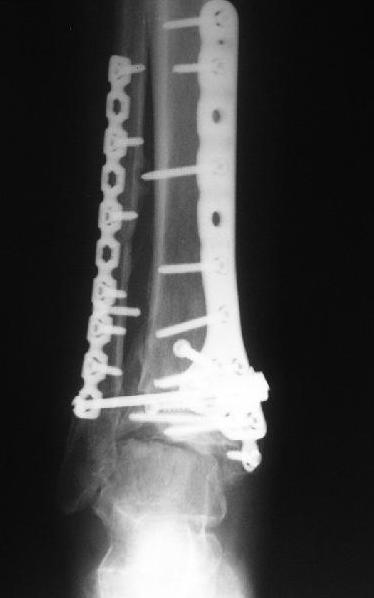

Dear коллеги,Обратилась женщина, 25 л. 8 мес. назад в одной из больниц сделан остеосинтез пилона. На сегодня ходит без дополнительной опоры, хромая на поврежденную ногу. Движения в голеностопном суставе еще есть. Снимки в приложении.

A female, 25, 8 month ago operated elsewhere. To date walks without support with pain and limp. The ankle is mobile yet. Images attached.The question is what to do now? The patient is not very keen on ankle fusion (though likely could change her mind if necessary)Is it worth to try a reconstruction procedure and what kind? Maybe it allows to restore alignment and tibio-fibular relationship - will it provide painless limb for more or less significant time?Or just remove the hardware and leave her alone until she herself comes for fusion?

She has an intraarticular screw on CT, best is to remove all and wait untill she asks for fusion.

CT images/xrays confirm incongruity of articular surfaces as well as intraarticular screws.

removing just those screws which have penetrated the joint may take some pain away.

Александр, добрый вечер! К сожалению, боюсь, что, кроме артродеза, ничего не осталось, упущено время. Просто убрать железо конечно можно, а куда деть вальгусную установку, "синдесмоз", признаки артрофиброза, которые прослеживаются на представленных рентгенограммах. Вопрос же стоит в качестве жизни пациентки, может ей тактично все объяснить, что чем дольше она будет так ходить, тем возможно болевой синдром будет более стойким и усилится деформация.